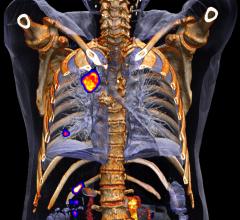

Calypso Medical Technologies, Inc. officially launched its recently FDA 510(k) cleared Calypso 4D Localization System at ASTRO, providing a new technology for real-time target localization and tumor tracking for a variety of clinical applications.

The 4D Localization System utilizes electromagnetic technology in conjunction with Calypso’s implanted Beacon Electromagnetic Transponders, in the prostate, to provide tumor location information during external beam radiation therapy without adding ionizing radiation.